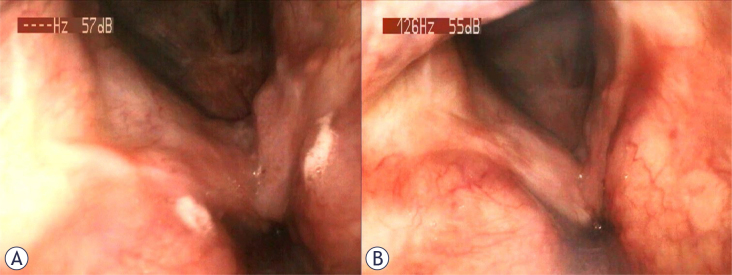

背景:复发性呼吸道乳头状瘤病(RRP)是由人乳头状瘤病毒(HPV)感染引起的一种疾病。治疗方法尚不明确,保守手术通常是保持呼吸功能的最佳选择。迄今为止,单克隆抗体被认为是一种既有效又安全的治疗选择。材料和方法:以“呼吸道或喉乳头状瘤病”和“HPV呼吸道感染、乳头状瘤病治疗、乳头状瘤病疫苗免疫、乳头状瘤病全身治疗”为检索词,检索MEDLINE/PubMed图书馆2000 - 2024年英文论文。此外,还对原始文章中的参考文献进行了人工筛选,以确定其他研究。我们选择了34篇文章。结果:自2009年以来,贝伐单抗已被用于治疗对手术治疗无反应的RRP。抗vegf单克隆抗体在RRP病变中的疗效可能与其血管性质有关。主要关注的是停止治疗后乳头状瘤的反弹生长。一个有趣的解决方案可能是同时使用免疫疗法,既减少残留疾病的负担,又激活免疫系统,对抗hpv感染的细胞。结论:贝伐单抗具有短期局部根除HPV的安全性。需要进一步的前瞻性研究和长期随访,以更好地确定其安全性和预防疾病复发的效果。考虑到抗hpv疫苗在预防感染和辅助设置中的作用,实际数据强调需要评估其对RRP管理的治疗效果。

Results: Since 2009, the systemic administration of Bevacizumab has been used to treat RRP not responding to surgical treatment. The efficacy of an anti-VEGF monoclonal antibody in RRP lesions can be related to their vascular nature. The major concern is the rebound papilloma growth within the cessation of treatment. An interesting solution could be the concomitant use of immunotherapy to both reduce the burden of residual disease and activate the immune system against the HPV-infected cells.